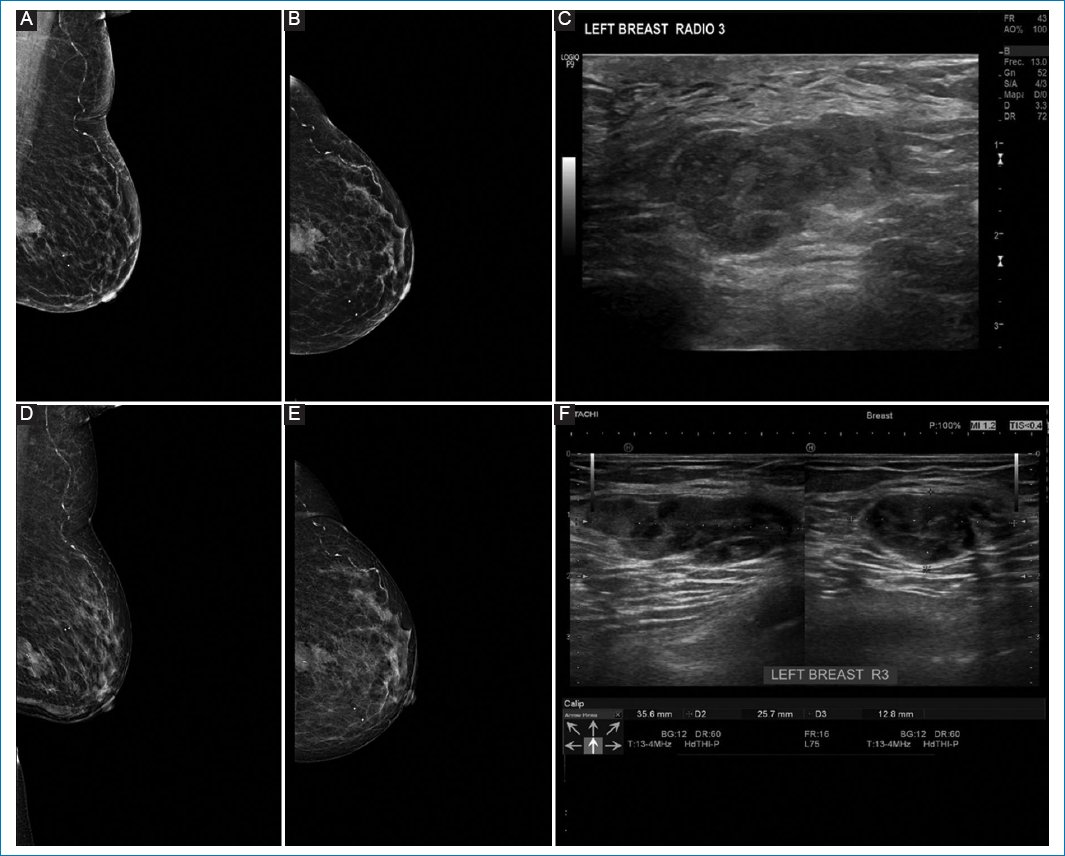

Pathologic response by imaging was classified as partial in 55.8% of cases (Figs. 1 and 2), complete in 34.6% (Figs. 3 and 4), stable (Fig. 5), or progressive disease in 9.6%. By pathology (RCB), response was complete in 53.8%, partial in 34.6%, and progressive in 11.5% (Fig. 6).

Figure 3. A-C: pre-neoadjuvant images. D-F: post-neoadjuvant images. 41-year-old woman diagnosed with right breast cancer, clinical stage IB by T1cN0M0, Luminal B with low hormone receptor expression, estrogen receptor 0%, PR 5%, human epidermal growth factor receptor 2 not amplified (Silver in situ hybridization) KI67 80%. A and B: shows pre-neoadjuvant mastography, with irregular nodule, in lower inner quadrant, showing intratumoral clip. C: ultrasound same patient with irregular nodule in R7 at 60 mm from the nipple. D and E: show mastography with clip, no nodule is visualized. F: breast ultrasound in R7 at 60 mm from the nipple, without presence of nodule. Images correspond to complete pathologic response corroborated by pathology.